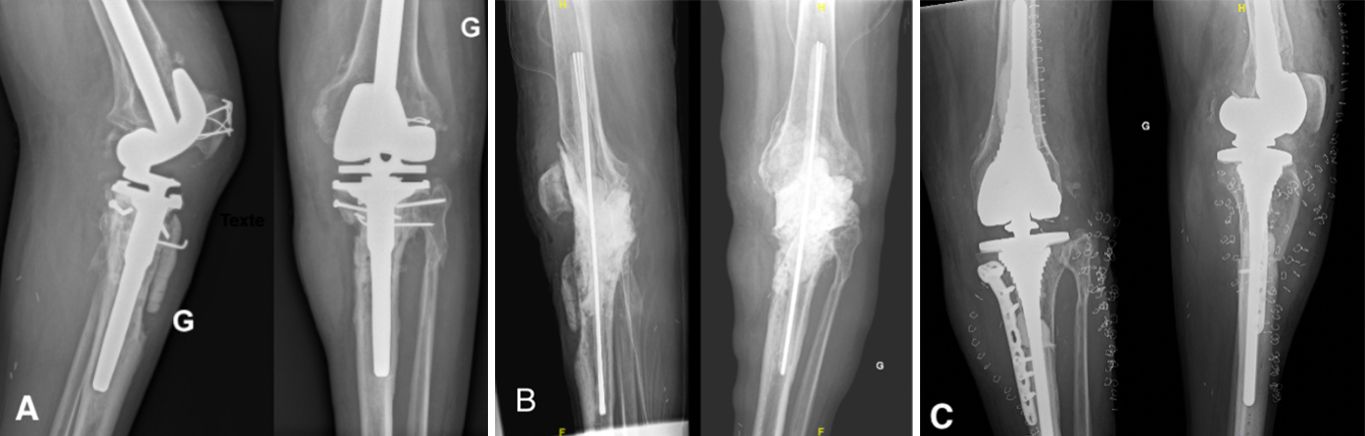

Antibiotic-impregnated cement spacers can be either static (non-articulating, block spacer) or dynamic [10]. Static spacers consist of a single block of cement inserted between the femur and the tibia (Case 1.B, 2.B, 3.B). It is non-articulating, fills the joint space and constitutes a temporary knee arthrodesis keeping the knee in full extension. This temporary immobilization leads amongst other things to joint stiffness and exposure difficulties at the time of reimplantation [9, 22, 23]. This increases the difficulty of prosthesis reimplantation and is associated with poorer clinical outcomes such as stiffness.

- Major bone loss, which is associated with a high risk of fracture, as well as a lack of fixation for a dynamic spacer (Cases 1-3).

- An incompetence of the collateral ligaments or the extensor mechanism, which can cause femoro-tibial dislocation with a dynamic spacer (Case 3).

During the second stage of surgery, the surgeon removes the cement by breaking the spacer and removing the rod spacer. It is easier to cut the wires and remove the rod in 2 parts. Another thorough debridement is performed and samples are taken before implantation of the new definitive prosthesis.